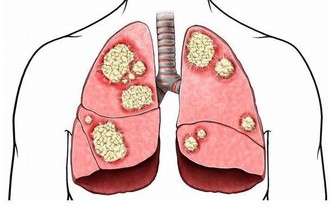

大部分患上中風的人一般都有如下特徵:身材肥胖,血壓高,患有多種心腦血管疾病,最常見的就是冠心病,動脈硬化,糖尿病。從根本上就要把血壓穩定在一個固定值,不能使血壓一直上升,除此之外,還要及時的治療這些心腦血管疾病,即使已經是無法治癒的話,也要穩住病情不能讓其繼續嚴重下去。堅持去測量血壓,長期堅持不降壓藥。